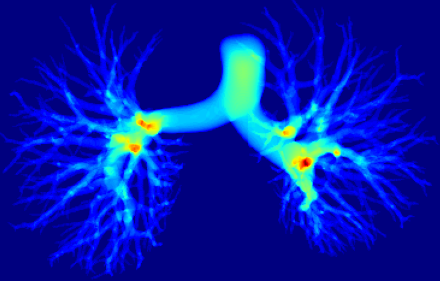

However, current state-of-the-art methods of lung organ segmentation still face several challenges and aspects for improvement. Firstly, the unlimited voxel values, multi-site imaging discrepancy and class imbalance in lung organ images can lead to false-negative and leakage issues in prior segmentation methods, which badly influences the critical early diagnosis of imperceptible lung diseases, e.g., lung fibrosis, nodule and hypertension, etc. Secondly, the presence of numerous slender branches, e.g., bronchioles and arterioles, which are easily lost during the recycled down/up-sampling procedure in Fig. 1, can result in discontinuity, detail loss, and coarse mask predictions. Thirdly, most CNN-based medical segmentation methods treat all points equally during the mask rendering stage, overlooking the vulnerability of border points in Fig. 1 (f) and the importance of explicit border modeling. Lastly, while Vision Transformer (ViT) has shown promise in computer vision tasks [1, 4], its quadratic operation complexity limits its application in 3D high-resolution CT images due to hardware constraints. Meanwhile, most specific datasets for medical image analysis are small and scarce due to laborious manual annotation and privacy protection, which badly restricts the potential of transformer-based top-tier methods.

2.2 Global-Local Cube-tree Fusion

where [0, 1] are the learnable coefficients to balance the importance of each feature; (6) we lastly add the feature to the relative position embedding features (retaining the topology information for inductive bias) for the voxel-wise decoding and refined prediction. Obviously, our proposed global-local cube-tree fusion module focuses merely on all border vulnerable points in Fig. 1(f) rather than all regular dense points in Fig. 1(c), which is more related to the lung organ regions. Experimental results demonstrate the efficacy of this design.

Ablation studies. To verify the efficacy of each module, we perform the thorough ablation studies in supplementary Tables 3-5 and Figs. 7-8. In Table 3, the 2-th row on lung fibrosis dataset with the proposed FA-based transformer-like backbone achieves the largest 2.24% CCFs, verifying the efficacy of fusing fuzzy sets and deep network to diminish the uncertainty in feature representations significantly. The 3-th row with GLCF module indicates 1.02% CCFs, proving that we only need to focus much on the very hard BVP rather than all regular dense points, which provide the most important losing information of discontinuity or details in the network down-sample operation. Since we only extract the BVP to render, it can suppress the redundant background to further solve the severe class imbalance issue of foreground and background voxels. Supplementary Table 4 evidences the efficacy of GLCF module which improves the border accuracy obviously by 4.72%. In Table 5, the 2-th row with FA-based transformer-like backbone improves the DBR significantly on the terminal (1.8%), small (1.25%) and medium (1.65%) branches except the large trachea (-1.03%), for most uncertainty in the feature representations is from the terminal, small and medium branches that are too thin and hard to be discerned while annotating. The 3-th row with GLCF module realizes the significant promotion of DBR on the small (2.02%), medium (2.02%) and large (3.09%) branches, which is consistent with Fig. 8 to overcome the issue of detail loss in the network down-sample operation and render the BVP effectively. Supplementary Fig. 7 elucidates that our FA-based transformer-like backbone can enhance the feature representations of lung organs significantly.